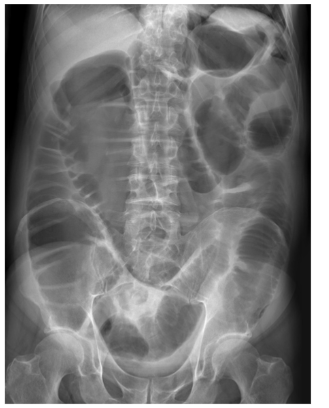

Patient with severe abdominal pain. What does the image show?

Ascites

Thumbprinting

Inflammation of the bowel wall leads to thickening of the haustral folds. This results in the radiological sign of thumbprinting, a characteristic finding in patients with active ulcerative colitis.